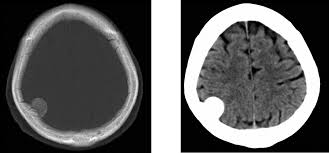

Acetato de medroxiprogesterona de depósito y riesgo de meningioma

En este estudio, las mujeres que recibieron acetato de medroxiprogesterona de depósito presentaron un mayor riesgo relativo de diagnóstico posterior de meningioma, especialmente con exposiciones prolongadas e inicio de la medicación a edades más avanzadas. El elevado número necesario para producir daño sugiere un bajo riesgo clínico general. JAMA Neurology, 2 de septiembre de 2025.